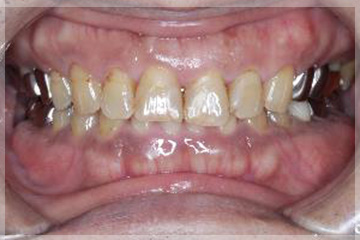

初診時